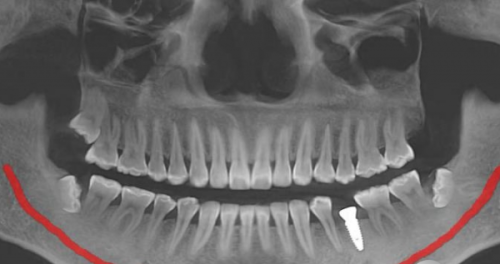

在种植牙方面,广州德伦口腔医院有着显著的优势。医生会根据患者的口腔情况和需求,选择合适的种植体,并且在种植过程中精细操作。特别多患者在德伦口腔做完种植牙后,都反馈成效非常好,牙齿功能修复正常,外观也十分自然。